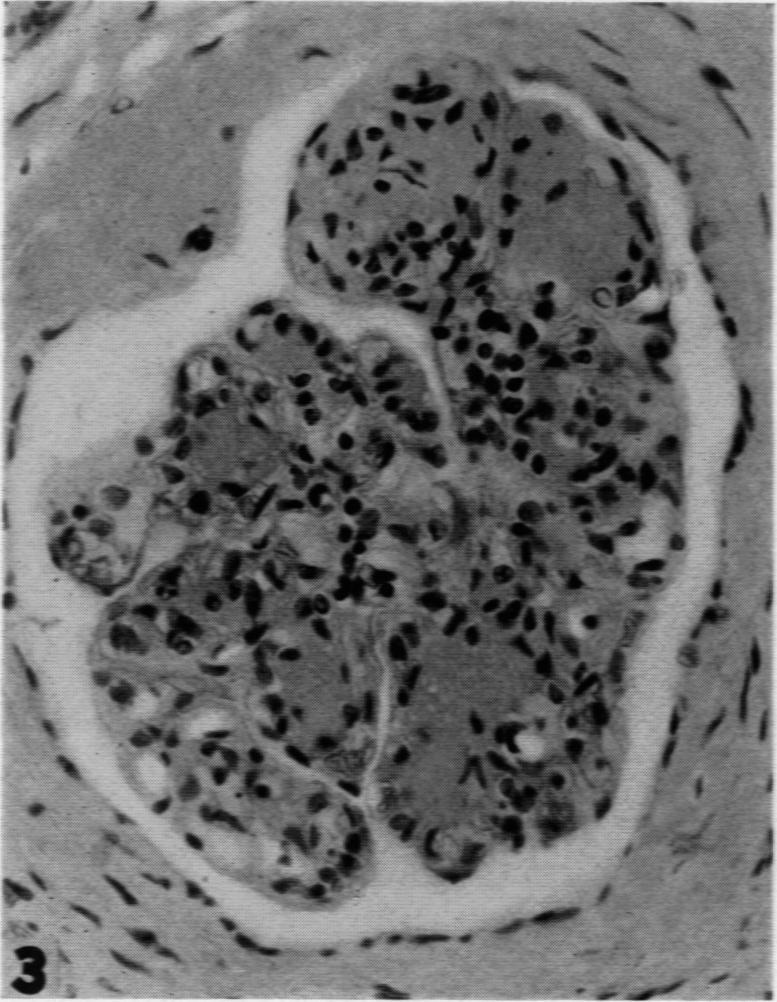

Intercapillary Glomerulosclerosis.

Am J Pathol. 1942 Jan;18(1):93-9.